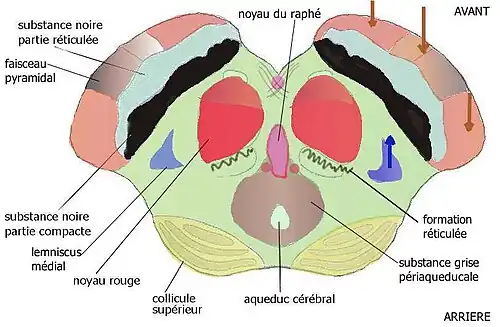

Crus cerebri

La crus cerebri (ou pied du mésencéphale) renferme des faisceaux cortico-pontiques, cortico-nucléaires et cortico-spinaux (faisceau pyramidal), et se trouvent séparés en arrière du tegmentum par la substantia nigra. Celle-ci est divisée en pars reticulata ventrale contenant des petits neurones gabaergiques se projetant sur le colliculus supérieur et en pars compacta dorsale, contenant de grands neurones dopaminergiques se projetant sur les ganglions de la base.

Tegmentum mesencephali

Le tegmentum contient :

- l'aqueduc de Sylvius (aqueduc du mésencéphale, en terminologie internationale) qui relie les troisième et quatrième ventricules, entouré de ;

- la substance grise périaqueducale (SGPA, en. PAG) qui contient des agrégats de neurones produisant de la sérotonine, de l'enképhaline, de l'endorphine, ou d'autres neuropeptides, jouant un rôle important dans le traitement des informations nociceptives ;

- l'aire tegmentale ventrale de Tsai ;

- les noyaux rouges parvo- et magno-cellulaires, intervenant dans les systèmes de rétrocontrôle positif et négatif de la motricité ;

- les noyaux cunéiformes et subcunéiformes de la formation réticulée ;

- le raphé médian mésencéphalique ;

- les noyaux oculomoteurs des 3e et 4e paires crâniennes, les noyaux du tractus optiques accessoires ;

- l'aire prétectale, ainsi que ;

- des faisceaux parmi lesquels les faisceaux :

- lemniscal latéral et médian, spino-thalamique, tegmental central et longitudinal supérieur, habénulo-interpédonculaire, et le pédoncule cérébelleux supérieur.

Tectum mésencéphalique

Le tectum (toit) est formé des deux colliculi supérieurs et des deux colliculi inférieurs formant la lame quadrijumelle.

Avant = ventral / Arrière = dorsal (faire un demi tour à la figure) |

Avant = ventral / Arrière = Dorsal (faire un demi tour à la figure) |

| Mésencéphale, coupe au niveau de la jonction pontomésencéphalique | Mésencéphale, coupe axiale au niveau du colliculus supérieur |